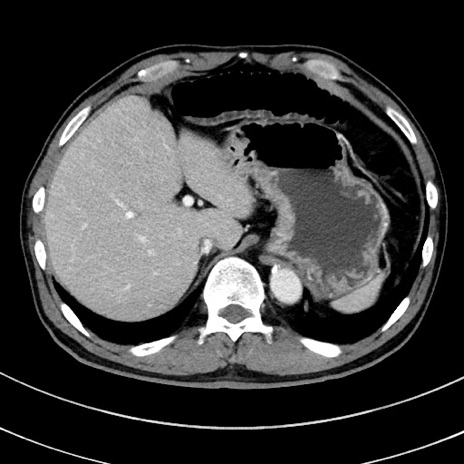

症例8(横断像)

【症例】 60歳代男性

【主訴】 黒色吐物

【現病歴】 4日前から嘔気自覚、2日前の朝食後にも嘔気あり、自分で手で嘔吐反射起こし嘔吐したところ血が混ざっていたため受診。

【既往歴】 5年前汎発性腹膜炎を伴う急性虫垂炎で手術、高血圧、前立腺肥大症、高脂血症

【身体所見】 腹部正中に手術癩痕あり 腹部平坦・軟圧痛なし膨満感あり

【データ】WBC 8400、CRP 4.54